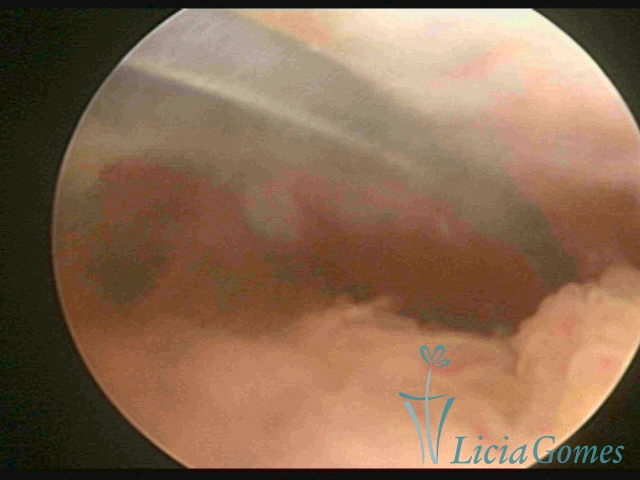

Canal cervical com fio do DIU